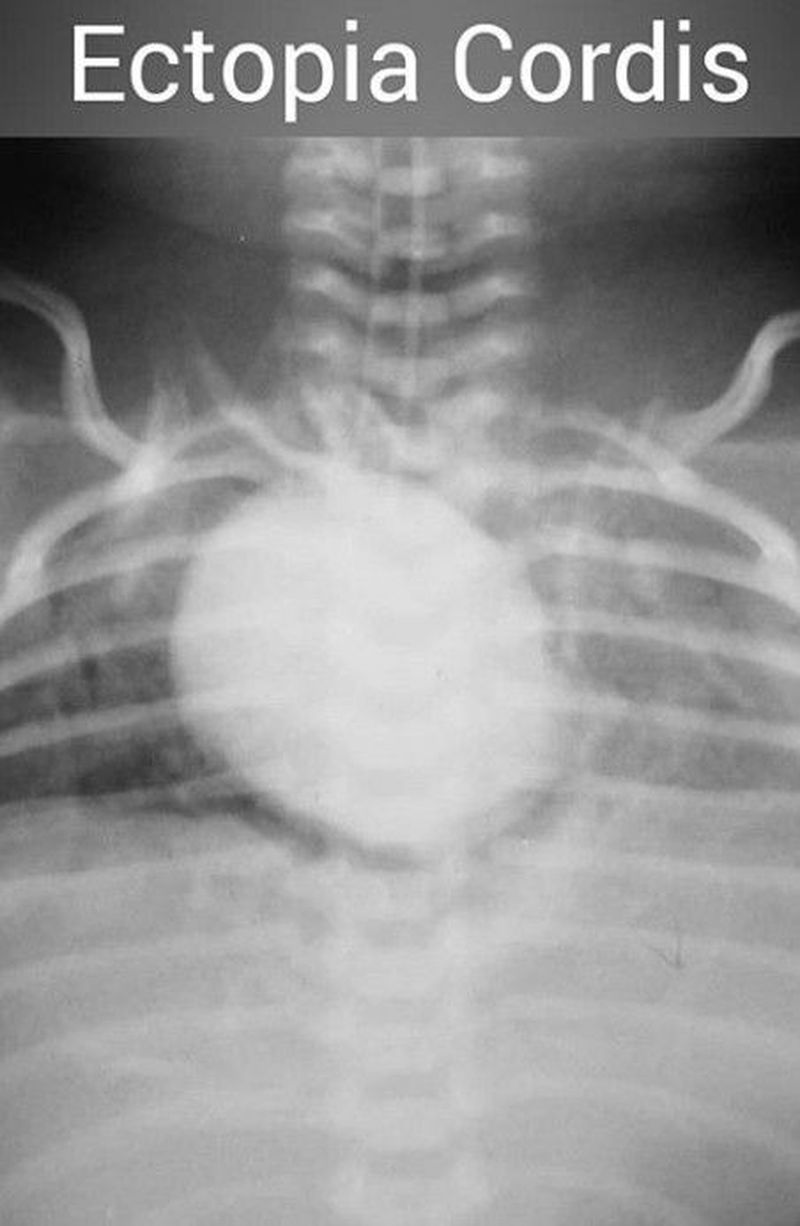

Ectopia cordis.

Ectopic cordis is an extremely rare conginital malformations where the heart is located partially or totally outside the thoracic cavity.